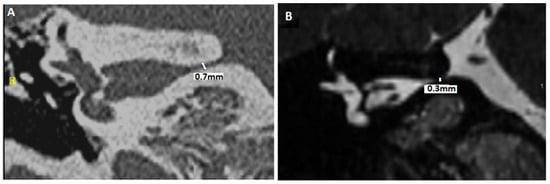

- Idriss, S.A.; Thai-Van, H.; Altaisan, R.; Ltaief-Boudrigua, A.; Reynard, P.; Ionescu, E.C. The Narrowed Internal Auditory Canal: A Distinct Etiology of Pediatric Vestibular Paroxysmia. J. Clin. Med. 2022, 11, 4300. [Google Scholar] [CrossRef]

- Ionescu, E.C.; Reynard, P.; Idriss, S.A.; Ltaief-Boudriga, A.; Joly, C.A.; Thai-Van, H. The “Near”-Narrowed Internal Auditory Canal Syndrome in Adults: Clinical Aspects, Audio-Vestibular Findings, and Radiological Criteria for Diagnosis. J. Clin. Med. 2023, 12, 7580. [Google Scholar] [CrossRef]

| - Evaluation of the smallest anteroposterior and craniocaudal IAC diameters (after measuring IAC length) - Description of bony abnormalities of the IAC walls (normal bone, fibrous dysplasia, meningeal calcifications, and/or osteoma of exostosis) - Evaluation of any significant angulation or deformation of the IAC (anteroposterior and craniocaudal planes) | - Assessment of the perineural fluid environment in the IAC - Angulation of the CVN? - Presence of NVCC? - Analysis of fusion images between high-resolution T2 and HRCT of the temporal bones - Evaluation of anteroposterior and craniocaudal diameters of the IAC |